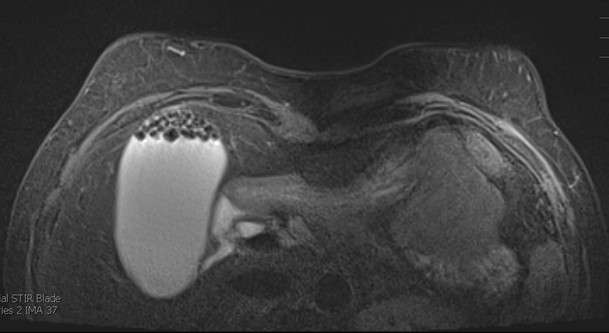

- In some cases, incidental liver findings demonstrate features of benignity and do not necessitate further work-up. For example, a well-circumscribed T2 /STIR-hyperintense lesion without enhancement consistent with a liver cyst, or a lesion with peripheral nodular discontinuous enhancement on multiphase contrast-enhanced breast MRI in keeping with a hemangioma do no necessitate further imaging (1).

- Other upper abdominal incidental findings include gallbladder pathology such as cholelithiasis or biliary pathology, as demonstrated in Figure 1, a patient with cholelithiasis and biliary ductal dilation.